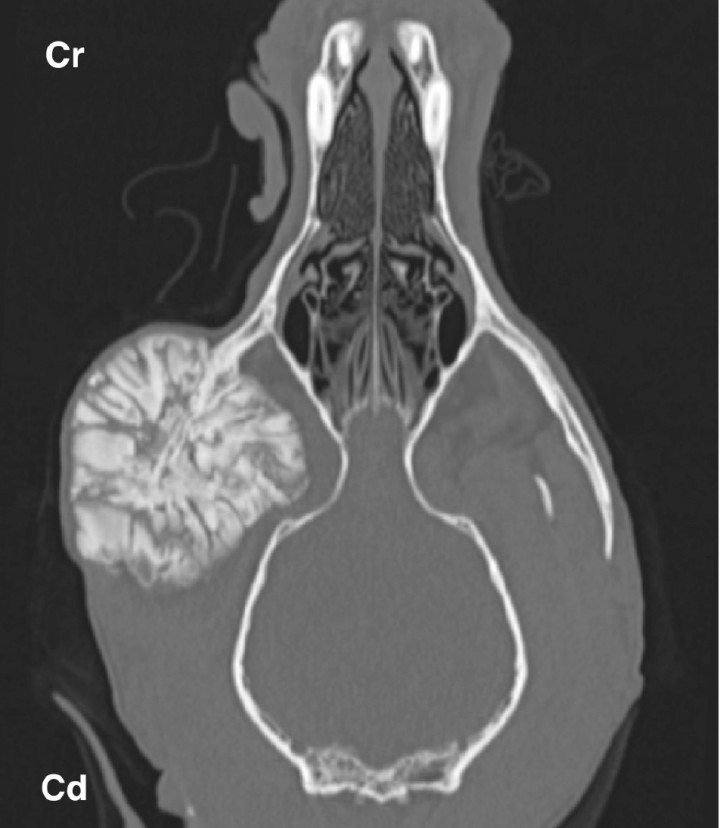

<p>Multilobular tumor of bone in an 8 year-old mixed breed dog. Dorsal bone window image of a head show a large, coarse, mineral attenuated mass with well defined margins at the level of the right zygomatic arc. Cr: cranial. Cd: caudal.</p>

Figura 2

Multilobular tumor of bone in an 8 year-old mixed breed dog. Dorsal bone window image of a head show a large, coarse, mineral attenuated mass with well defined margins at the level of the right zygomatic arc. Cr: cranial. Cd: caudal.

CT is also commonly used in characterizing skull tumours due to the complexity of this region. Although tissue sampling is paramount to obtaining an accurate diagnosis, some tumours have specific CT imaging characteristics, such as multilobular osteochondrosarcoma showing a fine to coarse granular, nonhomogeneous bone mass with well defined margins usually in the occipital region or at the level of the zygomatic arch (Fig. 2).[ Hathcock JT, Newton JC: Computed tomographic characteristics of multilobular tumor of bone involving the cranium in 7 dogs and zygomatic arch in 2 dogs. Vet Radiol Ultrasound 2000; 41: 214-217. [PubMed] ] In particular to assess for oral masses, CT is an important modality for preoperative purposes that gives valuable information about extent and a possible infiltrative nature.[ Ghirelli CO, Villamizar LA, Pinto AC: Comparison of standard radiography and computed tomography in 21 Dogs with maxillary masses. J Vet Dent 2013; 30:72-76. [PubMed] ] Besides, CT has been shown to more confidentially identify nasopharyngeal masses as polyps despite their typical location by a characteristic CT feature. A recent study reported the described rim enhancement of nasopharyngeal polyps in cats to represent a zone of inflammation.[ Lamb CR, Sibbing K, Priestnall SL: Pathologic basis for rim enhancement observed in computed tomographic images of feline nasopharyngeal polyps. Vet Radiol Ultrasound 2016; 57:130-136. [PubMed] ]